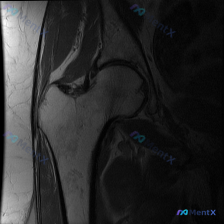

最近看到一份髋关节MRI分析的病例材料,有几个点值得讨论: 该影像为髋部MRI T1序列冠状位,报告提到股骨头内有典型的“新月征”(软骨下骨折线),提示缺血性坏死可能;同时也指出盂唇病变(撕裂/退变)的可能性。 问题1:仅凭这张T1序列,最应该优先考虑哪个诊断? 问题2:评估盂唇病变还需要完善哪些序...